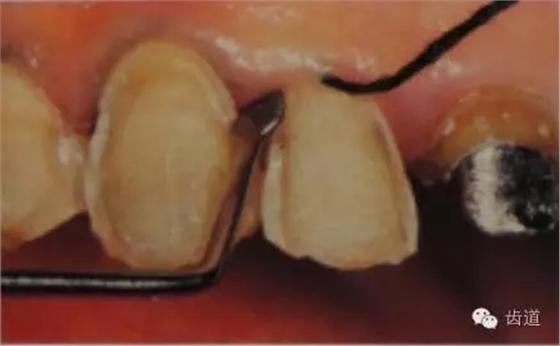

5、齦緣制備:通常瓷貼面的齦端邊緣位于齦上近齦緣處,但當(dāng)美觀要求時(shí)也可以設(shè)計(jì)在齦下0.5mm。

預(yù)備齦下邊緣之前要先排齦,之后選用圓頭錐形車針磨除牙體到所設(shè)計(jì)的邊緣位置。

1)排齦

2)制備